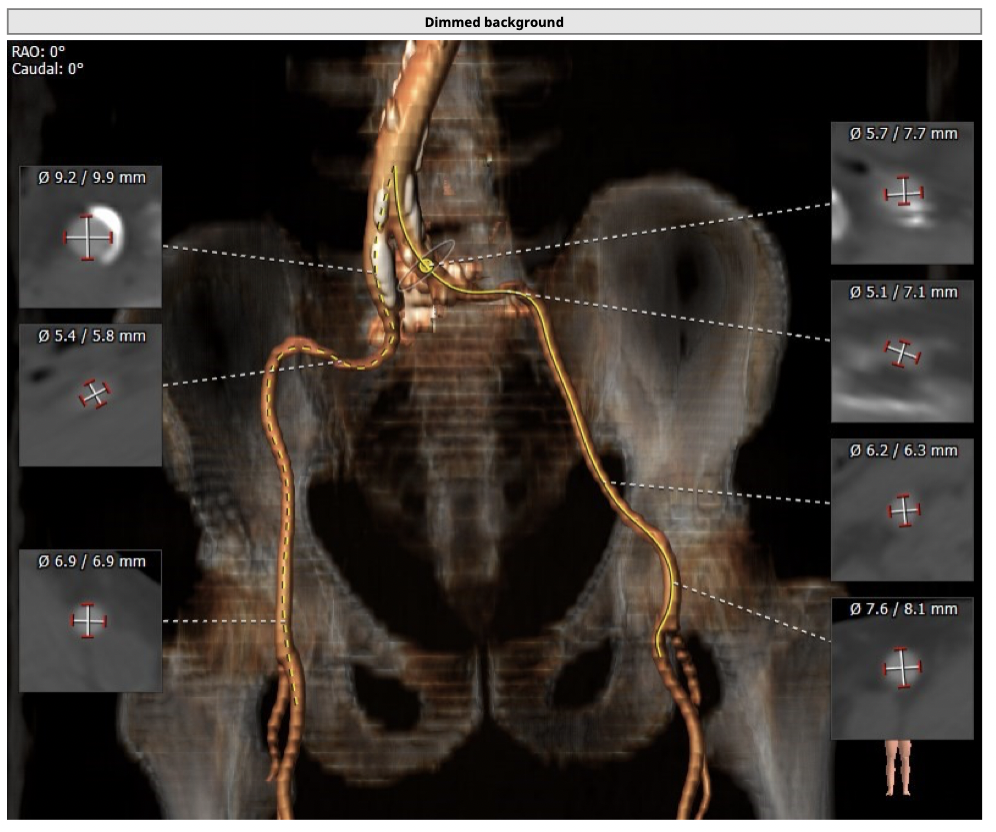

主动脉CT

图片

*功能型二叶瓣,瓣叶增厚,重度钙化,瓣环及左室流出道层面仍可见钙化,左右可见钙化融合,瓣膜释放后发生瓣周漏的风险较高,瓣膜释放后容易移位。

*左右股动脉较细,直径小于6mm, 双侧髂动脉-股动脉走形迂曲,可见明显钙化,术中操作需谨慎轻柔,注意血管并发症的发生。

经分析研判,拟从右侧股动脉穿刺入路,使用22mm球囊预扩,选用L26号的VenusA-Valve瓣膜,采用VenusA-Plus可回收输送系统进一步确保手术安全,瓣膜释放后结合造影和超声情况,决定是否后扩。